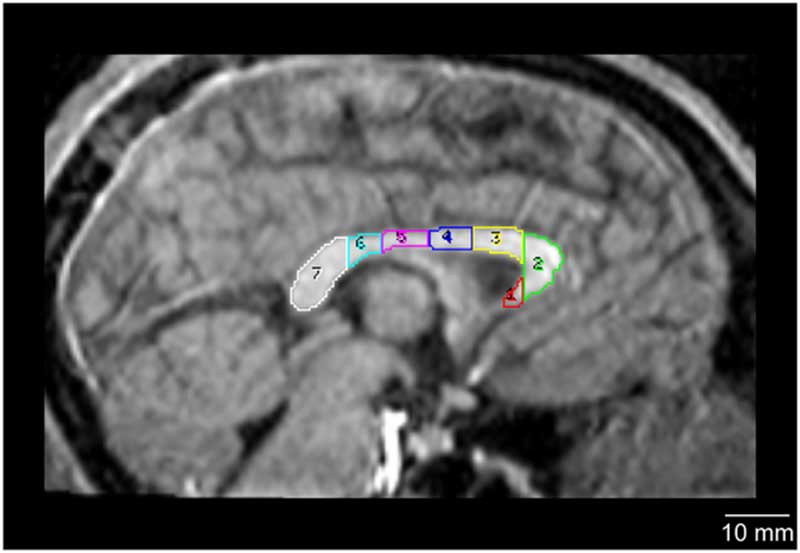

図:右側からみたチンパンジーの脳梁。七つの領域に分かれる。

1(赤)=rostrum、2(緑)=genu、3(黄)=rostral body、4(青)=anterior midbody、5(マジェンダ)=posterior midbody、6(シアン)=isthmus、7(白)=splenium